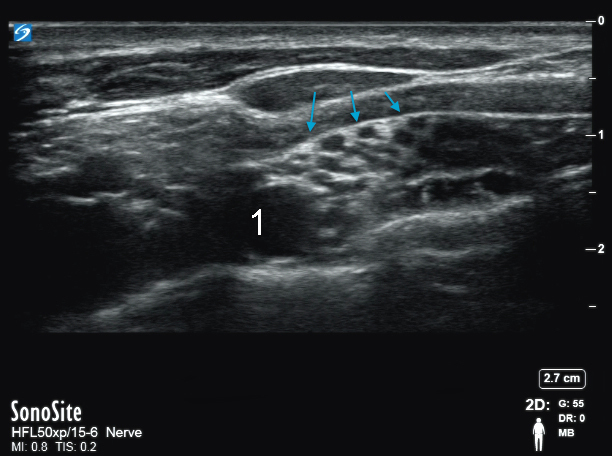

Bild: Supraklavikuläres Nervenbündel

Blaue Pfeile: Nervenbündel

Arteria supraclavicularis (ASC)